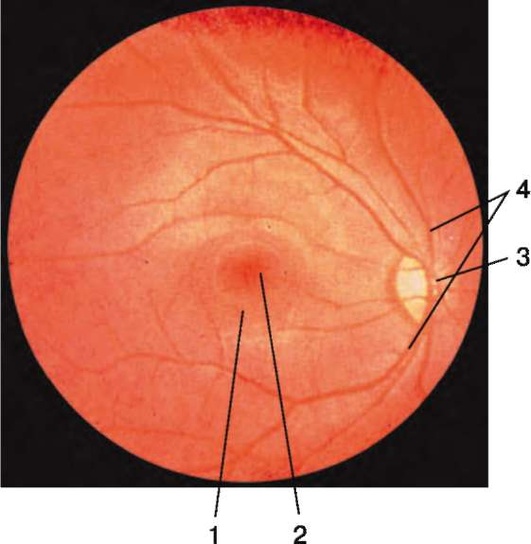

Рис. 1.4. Офтальмоскопическая картина нормального глазного дна: 1 - желтое пятно; 2 - центральная ямка желтого пятна; 3 - диск зрительного нерва; 4 - сосуды глазного дна